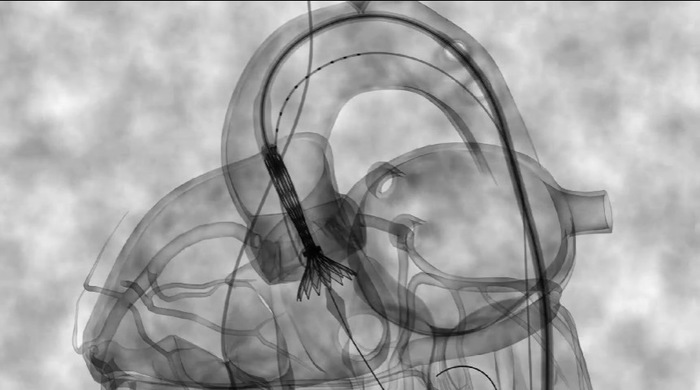

Десятки тысяч пациентов могут избежать открытой операции на открытом сердце

Замена аортального клапана минимально инвазивной процедурой под названием ТИАК (транскатетерная имплантация аортального клапана) оказалась очень эффективной альтернативой открытой хирургии.

Операция является минимально инвазивной: чтобы заменить неисправный аортальный клапан, кардиологи проводят операцию через мини доступ в области паха или бедра, и, по сосудам доходят до сердца, чтобы заменить клапан на новый.

При ТИАК единственным разрезом является небольшое отверстие в паховой или бедренной области, в которое вставляется специальный катетер. Традиционная операция включает в себя стернотомию  - распиливание грудины, разведение ребер и, в дополнение, остановку сердца, чтобы установить новый клапан.

Процедура, называемая Транскатетерная имплантация аортального клапана ( transcatheter aortic valve replacement, TAVR ), была предназначена в основном для пожилых и декомпенсированных пациентов, которые могли не пережить операцию на открытом сердце. Теперь два больших клинических испытания показывают, что ТИАК так же имеет место применения у более молодых пациентов.

Эти данные говорят о том, что предлагается более низкий риск осложнений, инсультов и смертельных исходов по сравнению с операцией на открытом сердце. Кардиологи говорят, что это, вероятно, изменит стандарт лечения для большинства пациентов с недостаточностью аортальных клапанов.

Большинство пациентов могу переносить процедуру под местной анестезией или легкой внутривенной седацией. Выздоровление занимает всего несколько дней, а не месяцев, как это часто бывает после обычной операции на сердце.

Ожидается, что данная процедура будет утверждена для пациентов с более низкими рисками для открытой хирургии.

Целых 20 000 пациентов в год будут иметь право на ТИАК, в дополнение к почти 60 000 пациентов среднего и высокого риска, которым проводится эти операция сейчас. (Данные из американских научных исследований)

Не смотря на это, некоторым, более молодым пациентам, по-прежнему нужна традиционная хирургия. ТИАК не был протестирован у этих пациентов, хоть эти состояния (например, двустворчатый аортальный клапан, в норме - он трёхстворчатый. Является врождённой аномалией, при которой клапан быстро изнашивается, вызывая сердечную недостаточность) чаще встречается у молодых пациентов с низким хирургическим риском.